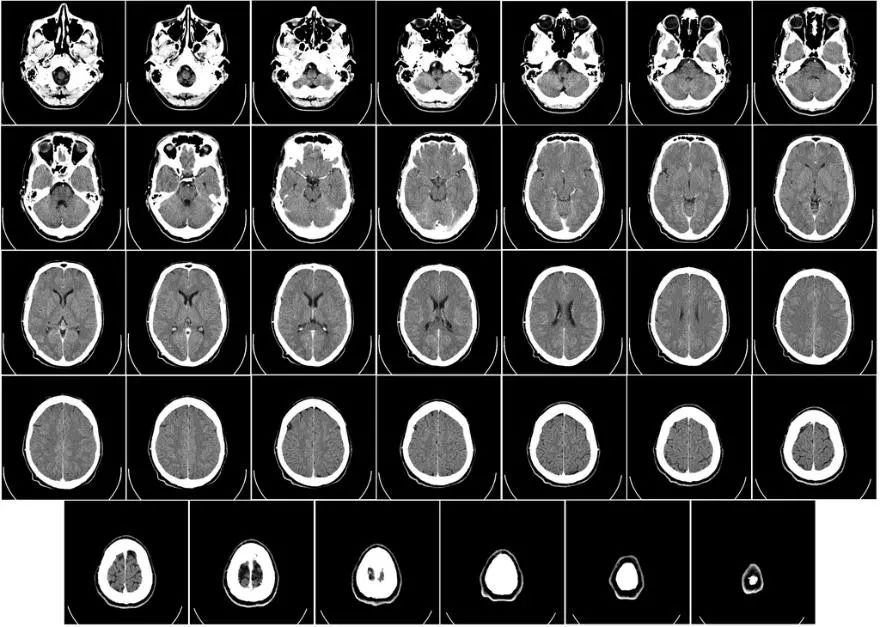

No.2 新程序加速脑部CT图像配准,一秒之内完成

图片来源:Wikipedia

在临床治疗中,医生会将患者不同时期的脑部CT图像进行配准对比(medical image registration),从而观察病灶微小的病变。不过这个过程非常耗时,每次至少要花费两个小时。为此,麻省理工学院的研究人员发布了一个新程序Voxel Morph,可用于实时配准脑部CT图像或其他3D图像。通过机器学习的方法,在配备了高端显卡后,Voxel Morph程序可以在一秒钟之内对图像进行配准,并且准确度完全不输传统方法。研究人员认为,这一新程序允许外科医生近乎实时地了解手术进展,有望极大加速某些手术的进程。